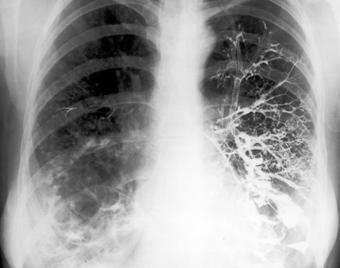

Fig. 24 – Metastaze pulmonare (opacitati nodulare si macronodulare multiple, diseminate pe ambele arii pulmonare, omogene, de intensitate medie, imprecis delimitate)

Din punct de vedere radiologic intalnim 3 forme:

- opacitati rotunde unice (metastaze solitare) situate in bazele pulmonilor;

- opacitati micronodulare pe toata aria pulmonara, ce apar in diseminarile hematogene;

- limfangita carcinomatoasa, caracterizata prin edem interstitial cu trabeculatii hilifuge si linii Kerley.